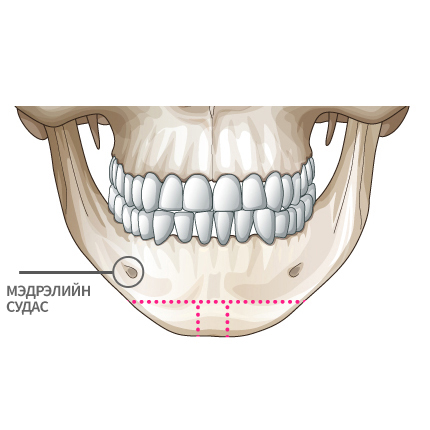

Mini V-line мэс заслын арга

Мэдрэлийн судаснаас зайлсхийж, эрүүний төгсгөлд зүсэлт хийнэ.

Ясны гол хэсгээс тайралт хийж авна.

Зүсэлт хийгдсэн эрүүний хоёр талыг нийлүүлнэ.

Эрүүний ясыг нийлүүлж тогтоож өгнө.

Хоёр хажуу талд товойж харагдах ясны хэсгийг тайрна.